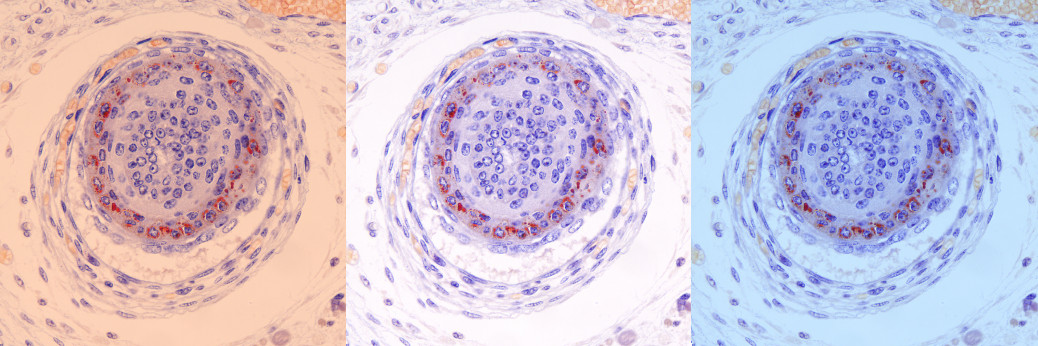

Objektiv Planachromat PLi 4x / Adapter 0,63x / MikroLive MultiFormat / Download der Originalaufnahme mit 5472 x 3648 Pixeln

Objektiv Planachromat PLi 10x / Adapter 0,63x / MikroLive MultiFormat / Download der Originalaufnahme mit 5472 x 3648 Pixeln

Objektiv Planachromat PLi 20x / Adapter 0,63x / MikroLive MultiFormat / Download der Originalaufnahme mit 5472 x 3648 Pixeln

Objektiv Planachromat PLi 40x / Adapter 0,63x / MikroLive MultiFormat / Download der Originalaufnahme mit 5472 x 3648 Pixeln

Objektiv Planachromat PLi 100x(Öl) / Adapter 0,63x / MikroLive MultiFormat / Download der Originalaufnahme mit 5472 x 3648 Pixeln